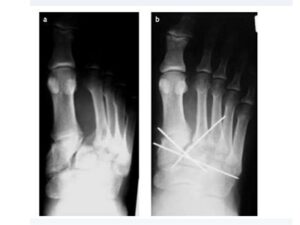

El esguince en la parte media del pie es una avulsión relacionada con los ligamentos que unen los cinco huesos metatarsianos a los cuatro huesos cuneiformes. El ligamento de Lisfranc puede aparecer, principalmente durante las actividades deportivas y puede conducir a una fractura del hueso cuneiforme medial al que se une.

Comúnmente, un esguince pequeño puede resultar en una avulsión completa ya que el segundo metatarsiano se vuelve inestable debido a la laxitud del ligamento de LisFranc. Estas fracturas generalmente se deben a la compresión, el atrapamiento del pie y la caída directa sobre los dedos.

Un colapso del arco puede ocurrir si el esguince leve del ligamento se deja sin tratar y se juega constantemente. La cirugía puede llegar a ser necesaria, pero se pueden prescribir tratamientos alternativos que incluyen la manipulación, un yeso en el pie para restablecer los huesos y la observación de los períodos sin carga.